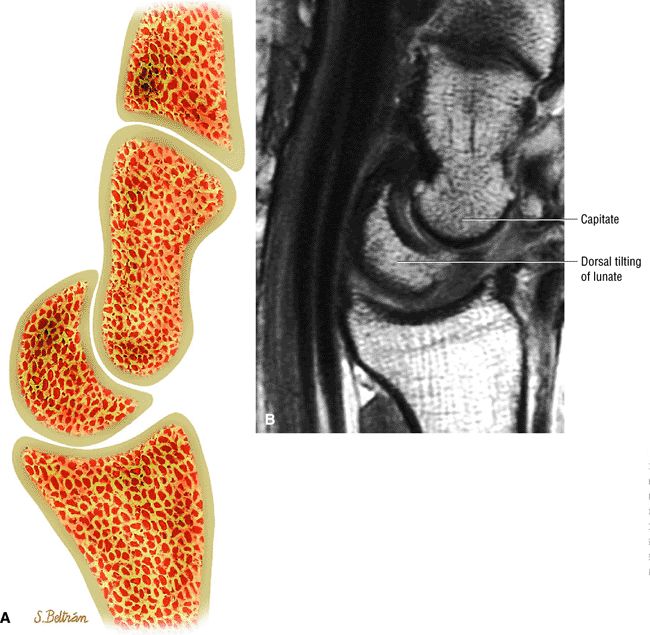

exceeds 30°. When DISI is present, the scapholunate ligament is evaluated for associated tears. The position of the scaphoid with respect to the rest of the carpus is also assessed. An anteriorly tipped or “flexed” scaphoid is an additional sign of DISI. When the lunate is tipped in a volar direction, with palmar translocation of the carpus, volar intercalated segmental instability (VISI) is suggested. VISI is associated with lunotriquetral ligament tears and dorsal extrinsic ligament injuries.

Scapholunate ligament diastasis with greater than 4 mm of diastasis of the scapholunate ligament. Superim-posed arthrosis of the capitolunate articulation.

DISI instability of the wrist with dorsal tilting of the lunate.

During lunate dorsiflexion, there is elevation of the distal pole of the scaphoid (i.e., scaphoid extension). Thus, in ulnar deviation, an extension torque predominates, and interaction at the triquetrohamate helicoid slope and proximal carpal row extension produces a physiologic DISI pattern.

DISI with dorsal tilting of lunate, an increased capito-lunate angle (more than 30°), and an increased scapho-lunate angle (more than 80°) (Fig. 10.98)